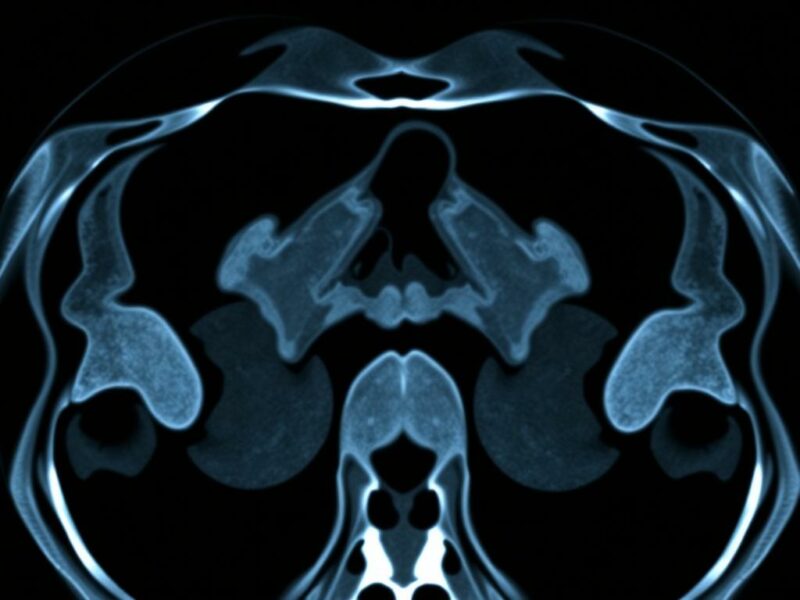

Cuando hablamos de IA en imágenes médicas nos referimos a un conjunto de técnicas que incluyen desde algoritmos clásicos de aprendizaje automático hasta redes neuronales profundas (deep learning). En el contexto de la TC abdominal para apendicitis, las tareas típicas que la IA aborda son la segmentación (localizar y delimitar el apéndice), la clasificación (decidir si hay apendicitis) y la detección de complicaciones (absceso, perforación, obstrucción intestinal asociada).

Las redes convolucionales (CNN) son las arquitecturas dominantes para imágenes: aprenden características directamente de los píxeles y pueden distinguir texturas, bordes y patrones complejos. Modelos más avanzados combinan CNN con enfoques de atención para centrar el análisis en regiones relevantes o usan redes 3D que procesan volúmenes completos de TC para conservar información espacial. Otra estrategia complementaria es la radiómica, que extrae cientos de características cuantitativas de las imágenes (formas, texturas, intensidad) y las usa en modelos estadísticos o máquinas de soporte vectorial. En la práctica clínica emergente, lo habitual es ver soluciones híbridas que combinan segmentación automática del apéndice, extracción radiómica y clasificación con redes profundas.